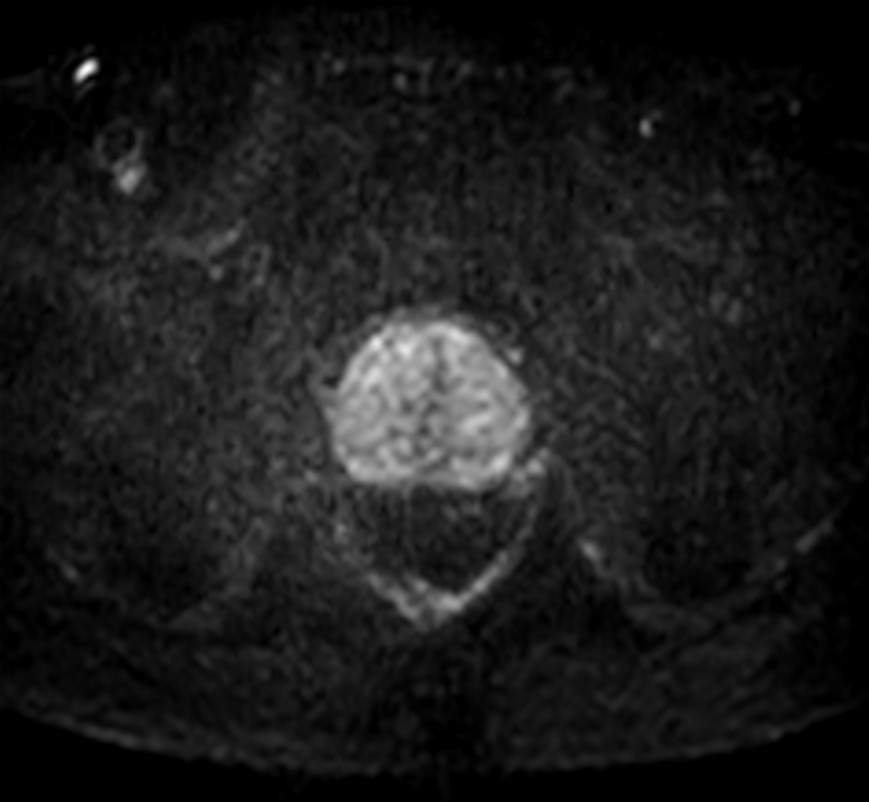

Fast Prostate imaging with SmartSpeed Precise

Kumamoto Chuo Hospital Japan